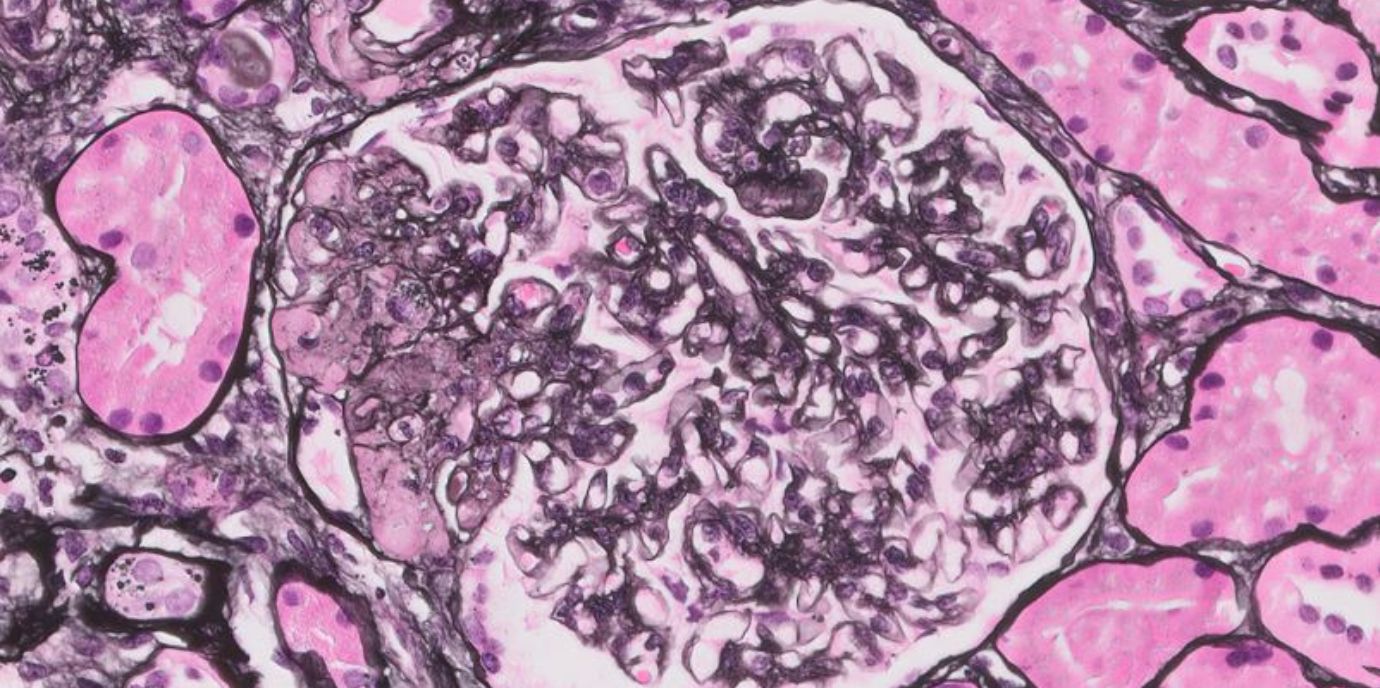

Vieles ist noch unerforscht bei Podozythopathien, zu denen die Formen Minimal Change Disease und FSGS (fokal segmentale Glomerulosklerose) zählen. Bei diesen seltenen Krankheiten werden die Filterzellen der Nieren (Podozyten) angegriffen. Wie viele Menschen davon betroffen sind, ist nicht genau bekannt. Vermutlich handelt es sich um Autoimmunerkrankungen. Es gibt starke Hinweise dafür. Doch auch das ist noch nicht restlos gesichert. Folglich gibt es keine zugelassene Therapie und schon gar keine, die auf die Ursache abzielen könnte. Jetzt aber stimmen die Ergebnisse einer retrospektiven Untersuchung, die an weltweit 30 Zentren in 15 Ländern und von insgesamt 52 Forscher:innen unter der Leitung von Philipp Gauckler (Erstautor) und Andreas Kronbichler (korrespondierender Autor) von der Univ.-Klinik für Innere Medizin IV (Direktor: Gert Mayer) durchgeführt wurde, zuversichtlich: In der Studie „Long-Term Outcomes of Rituximab-Treated Adult Patients with Podocythopathies“, die unlängst im hochrangigen Journal of the American Society of Nephrology veröffentlicht wurde, konnten die Forscher:innen zeigen, dass die Behandlung mit der Substanz Rituximab neben der guten Verträglichkeit noch weitere Vorteile für die Patient:innen bringt.

Sowohl Minimal Change Disease als auch FSGS äußern sich als nephrotisches Syndrom: Die Betroffenen dieser meist schubartig verlaufenden Krankheit verlieren akut sehr viel Eiweiß über den Harn. Innerhalb kürzester Zeit kommt es zu einer massiven Gewichtszunahme – teilweise zehn bis 15 Kilogramm binnen einer Woche – durch Wassereinlagerungen. An Beinen, Händen, Augen, oft auch im Bauchbereich entstehen massive Schwellungen. Der Blutdruck steigt. Menschen jeden Alters können betroffen sein. Im Gegensatz zu anderen seltenen Krankheiten kann die Diagnose recht einfach gestellt werden. Ein einfacher Harnstreifentest sollte ausreichen, um die Alarmglocken schrillen zu lassen, die enorme Ausscheidung von Eiweiß macht Mediziner:innen hellhörig.

Außerdem: „Bei Kindern ist Minimal Change Disease mit mehr als 90 Prozent die allerhäufigste Ursache von einem nephrotischen Syndrom, sodass man ihre Nieren eigentlich schon gar nicht mehr biopsiert. Mit zunehmendem Alter tritt diese Krankheitsform aber weniger auf. Die FSGS-Erkrankung kommt über alle Altersgruppen hinweg in etwa stabil vor und ist für 20 Prozent der nephrotischen Syndrome verantwortlich“, erklärt Philipp Gauckler. Das Therapieansprechen bei FSGS ist meistens schlechter als bei Minimal Change Disease. Sprechen die Patient:innen auf die Therapie nicht an, werden sie nach durchschnittlich sieben Jahren dialysepflichtig, selbst nach einer Nierentransplantation kehren in 30 bis 40 Prozent der Fälle die Krankheitsschübe zurück. „Auch deshalb geht man davon aus, dass es sich um eine Autoimmunerkrankung handelt. Wäre die Krankheit nierenassoziiert, würde es im Transplantat keine Rückfälle geben“, führt Andreas Kronbichler weiter aus.